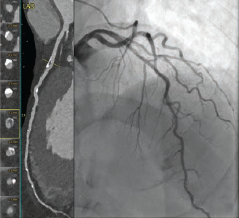

Coronary artery fistulas (CAF) are rare anomalies with variable presentations and complications including congestive heart failure, myocardial infarction, and arrhythmia depending on anatomy. Congenital etiologies account for the majority of...

Percutaneous coronary intervention (PCI) with metallic stents is the mainstay of revascularization for patients who present with angina where coronary artery bypass surgery is not indicated. Partial volume artifacts and blooming present...